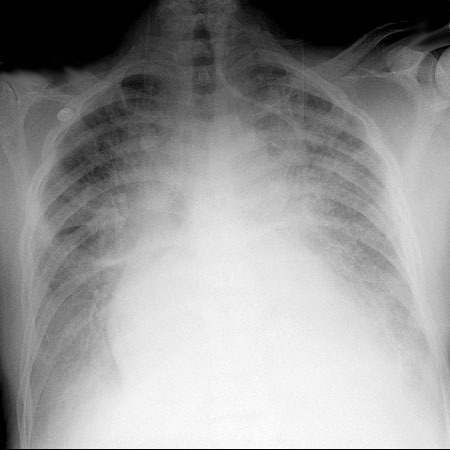

A 78-year-old male presents with increased SOB over the past 4 days. A recent ECHO will be presented showing severe AS. The ECG will demonstrate new A Fib with a HR of 150 and the CXR will show CHF. The patient will be normotensive at first but will become hypotensive shortly after. The team will then need to decide whether to cardiovert the patient or attempt rate control. If these are done safely, the patient will respond and then develop worsening CHF. Definitive management should be sought with early cardiology/cardiac surgery consult. If management is not carried out judiciously, the patient will become profoundly hypotensive.

CXR for the case found here:

(CXR source: https://www.med-ed.virginia.edu/courses/rad/cxr/pathology2Bchest.html)